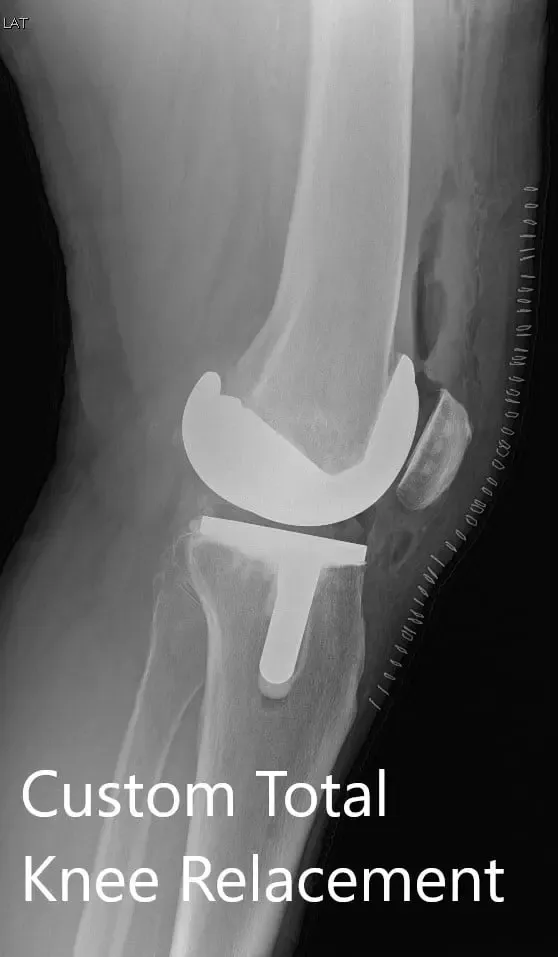

Postoperative X-ray showing AP and lateral views of the right knee

The recovery of the patient was unremarkable. She was able to walk the same day of the surgery. The pain was well managed with oxycodone and acetaminophen. Aspirin was used for DVT prophylaxis. The sutures were removed uneventfully.

The initial active range of motion was from 5 to 90 degrees which gradually increased to 3 to 120 degrees after a month of physical therapy. She demonstrated a full range of motion without any pain at her 3 months follow up visit. The patient was now back in her routine. She was happily doing yoga and enjoyed fencing as she did before the onset of pain.